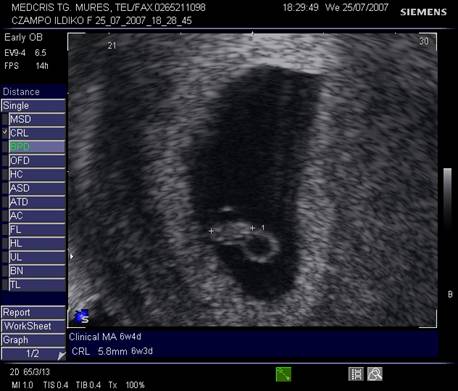

Fig nr. 12. Embrion corespunzator la 6 sapt si 3 zile

( masurat intre cele doua calipere )